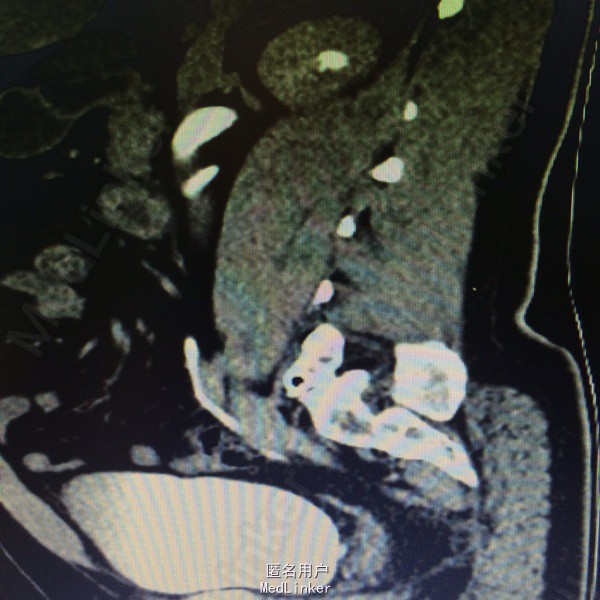

入院后查体,T 36.7℃,P 73次/分,R 21次/分, BP 130/90mmHg。全腹无压痛,反跳痛。右侧胆囊压痛点无压痛反跳痛。右侧腰部叩击痛阳性。右侧输尿管走形区无压痛叩击痛。外生殖器未见异常。 各项生化指标检验在正常范围,尿常规 RBC 阴性,WBC 阴性。泌尿系CTU检查:右肾肾盂及输尿管上段扩张积水,输尿管中段局部走形异常,中下段无明显扩张。左侧肾盂肾盏及输尿管未见明显异常密度影。膀胱充盈良好,未见异常密度影。增强:右侧输尿管上段局部弯折,弯折处狭窄,未走行于腰大肌前方,自下腔静脉后方向左侧,再向前走形。下段走行正常。左侧输尿管未见明显异常密度影。左肾未见明显异常密度影,右肾实质内可见一小圆形低密度影,无明显强化。诊断意见:右输尿管上段弯曲并走行异常,并上段输尿管扩张积水。右肾盂扩张积水,结合临床评估。2右肾小囊肿。

术前诊断:腔静脉后输尿管 处理:腹腔镜下右侧肾盂成形术,术中游离出扩张积水的肾盂及输尿管上段,在肾盂输尿管连接部离断。分离出下腔静脉后,将腔静脉后端走形的输尿管游离出,并游离整个输尿管至髂血管交叉处。将受压段的输尿管截断,修剪扩张的肾盂及输尿管,与游离的远端输尿管vy吻合成形,期间置入6F D-J管。术后5天拔除肾周引流管,留置尿管6天。

患者目前术后一月,拟于术后2月拔除D-J管,行静脉肾盂造影评估术后。 下腔静脉后输尿管是下腔静脉发育反常的一种先天性畸形。本病的主要病理改变是梗阻所致,由于输尿管受压梗阻造成尿液引流不畅,导致患者腰部或腹部钝痛,甚至绞痛;血尿是常见症状之一,一部分病人伴有泌尿系结石,虽然下腔静脉后输尿管是先天性畸形,但大多数病人都在成年后才出现症状。右侧输尿管于第三、四腰椎平面,从下腔静脉后方绕向前,再转向外侧正常途径进入膀胱。本病发病的原因是由于下腔静脉的胚胎发育异常而使得右侧输尿管上段的位置异常。右侧输尿管上1/3位于腔静脉之后,并环绕下腔静脉再回到其前面。由于上段输尿管受压或纤维化导致右肾积水。感染和结石。本病发展较慢,大多在成年后出现症状。手术治疗是主要手段,只要肾功能还未毁损,预后是良好的。本症多见于男性,男:女为3:1。典型病例是右侧输尿管绕过腔静脉之后走向中线,再从内向外沿正常路径至膀胱,肾盂及上段输尿管扩张。下腔静脉后输尿管分为2种临床类型:Ⅰ型,有肾积水及梗阻,梗阻近端输尿管呈鱼钩样,较常见;Ⅱ型,没有肾积水或仅有轻度肾积水,此型输尿管在更高位置走向腔静脉之后,肾盂及输尿管几乎呈水平位,无扭曲,如有梗阻是因位于腔静脉侧壁的输尿管受椎旁组织的压迫所致。 临床表现:右侧腰部顿性疼痛,并发结石者可出现肾绞痛。合并尿路感染可有发热、血尿。查体右肾区有压痛,叩击痛。诊断:并发肾积水、结石及感染时可有腰痛、血尿、发热及脓尿等。尿路造影可显示右肾积水及右输尿管呈“S”状或镰刀状弯曲。泌尿系造影显示右肾积水,右输尿管上段扩张,并向中线移位。 治疗:应在肾盂与输尿管连接处以上切断,切除不正常的输尿管段,将输尿管移至下腔静脉前行吻合。如术前肾积水严重,并有感染等,术前术后可用敏感的抗生素治疗,保证吻合口愈合良好。